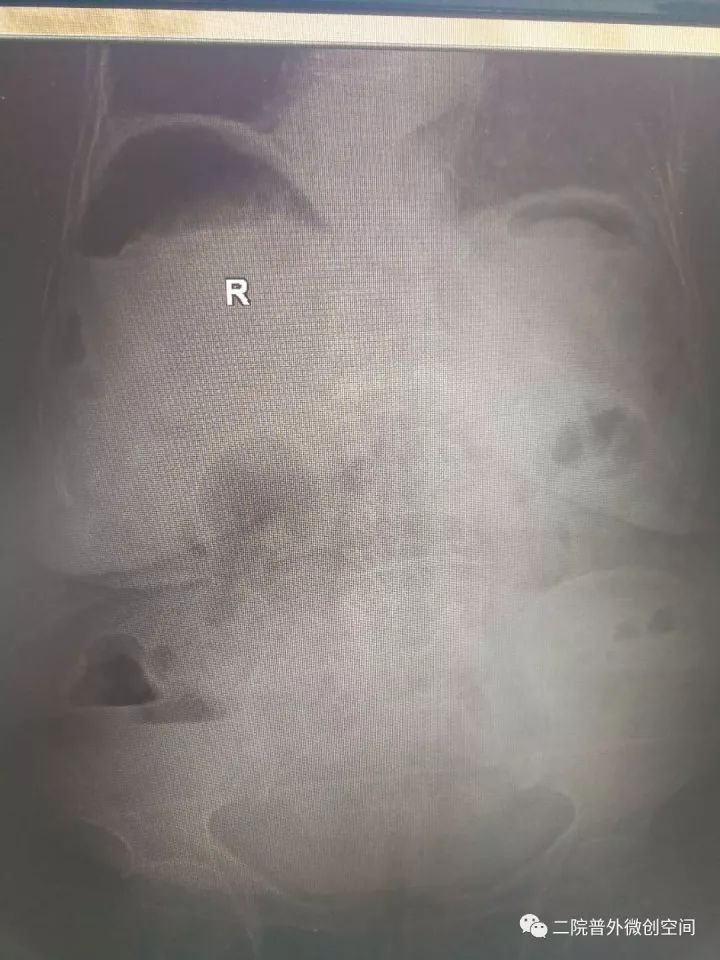

据悉,老奶奶月前摔伤而口服止痛药,2017年10月23日中午突然出现腹痛,逐渐加重,急到当地卫生院就诊,当地医生检视后考虑“急腹症”急转夏邑县第二人民医院普外科。入院后经副主任医师井晓亮检查后考虑消化道穿孔,治疗需手术治疗。

经过充分的术前准备,在麻醉科同事保驾护航下成功为患者施行了腹腔镜下胃穿孔修补术。麻醉及手术过程的艰巨程度可想而知——低血压、低血氧、腹腔充满脓液,穿孔大......而这些,在井晓亮主任、谢龙医师、王天琪医师的精细操作下一一化解!